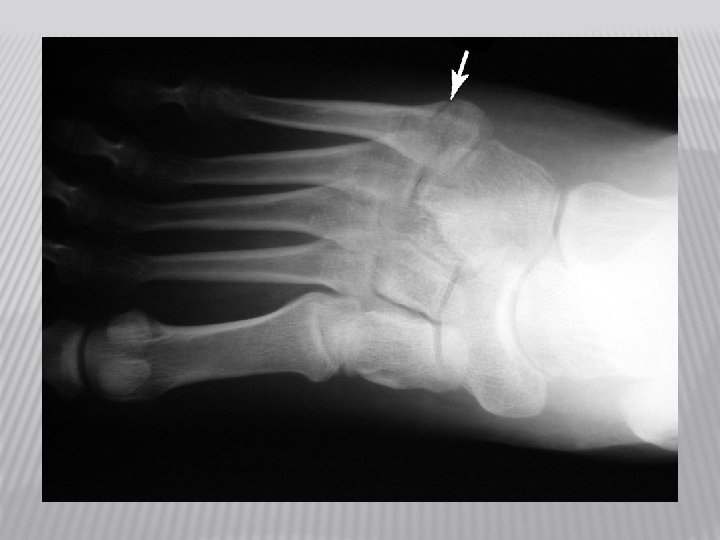

� Bunion (Hallux Valgus Deformity) � Cause of Injury � Exostosis of 1 st metatarsal head; associated with forefoot varus; shoes that are too narrow, pointed, or short � Bursa becomes inflamed and thickens, enlarging joint, and causing lateral malalignment of great toe � Sign of Injury � Tenderness, swelling, and enlargement of joint initially � As inflammation continues, angulation increases causing painful ambulation © 2005 The Mc. Graw-Hill Companies, Inc. All rights reserved.

� Care � Wear correctly fitting shoes, appropriate orthotics, pad over 1 st metatarsal head, tape splint between 1 st and 2 nd toe � Surgery may be required during later stages of condition © 2005 The Mc. Graw-Hill Companies, Inc. All rights reserved.